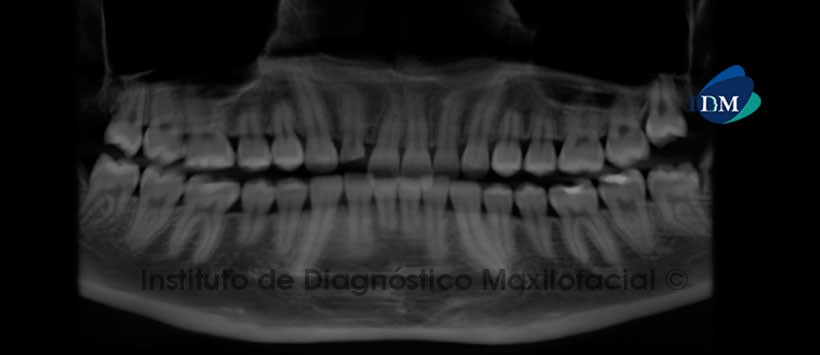

A la evaluación de la radiografía panorámica sólo se aprecia pérdida de estructura dentaria que compromete la corona de la pieza 1.2. Estructuras óseas aparentemente conservadas (Figura 1)